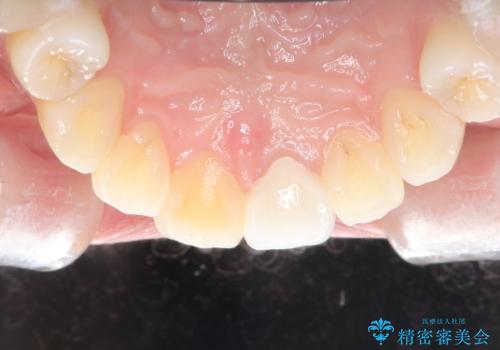

- 前歯が、ポロポロ欠けてくることを主訴で来院された女性です。

以前に根の治療しましたが、最近になって色なども気になり来院されました。

神経の治療をしている歯は、時間と共に色がどんどん変色していきます。

また、神経、血液供給がなくなってしまう影響から歯も脆くなっていってしまうため、歯が割れてしまうリスクもあります。